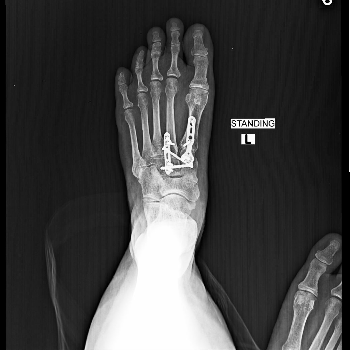

Lisfranc Injury Treatment

Lisfranc injury treatment includes immobilization, rest, pain management, and physiotherapy. Moderate to severe cases may require surgical fixation, followed by structured rehabilitation programs to restore stability, improve mobility, and ensure proper long term recovery.